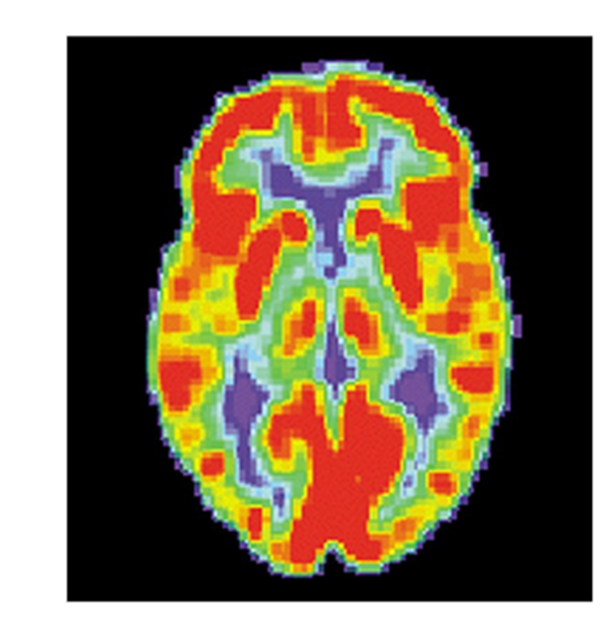

Functional Techniques:

PET (Positron Emission Tomography): Utilizes radiotracers to evaluate brain metabolism, measuring blood flow and abnormal protein deposits.

Page 21: Functional Brain Imaging Techniques

PET Scan Overview:

The PET scan evaluates physiological changes in the brain by measuring blood flow, allowing researchers and clinicians to infer areas of metabolic activity which correspond to neuronal function.